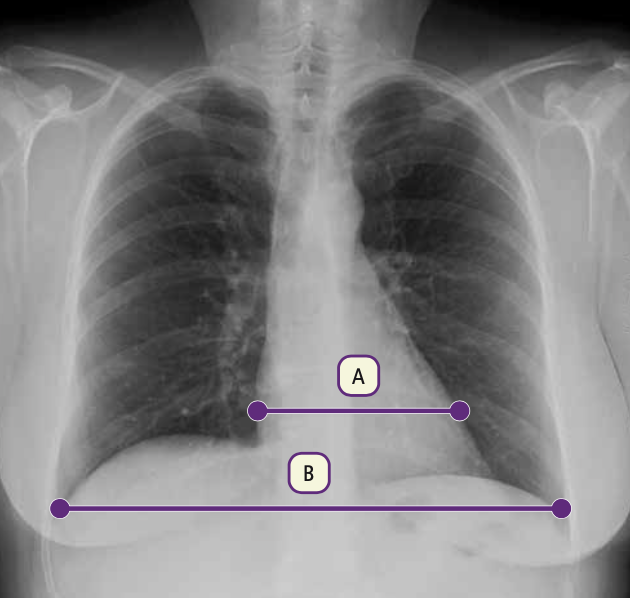

El índice cardiotorácico (ICT) es..

El índice cardiotorácico (ICT) es la relación que existe entre el diámetro transverso del corazón y el diámetro transverso del tórax. Para calcularlo mide la anchura horizontal del corazón y divídela entre el diámetro interno más ancho del tórax. Un índice cardiotorácico normal debe ser inferior a 0,5.